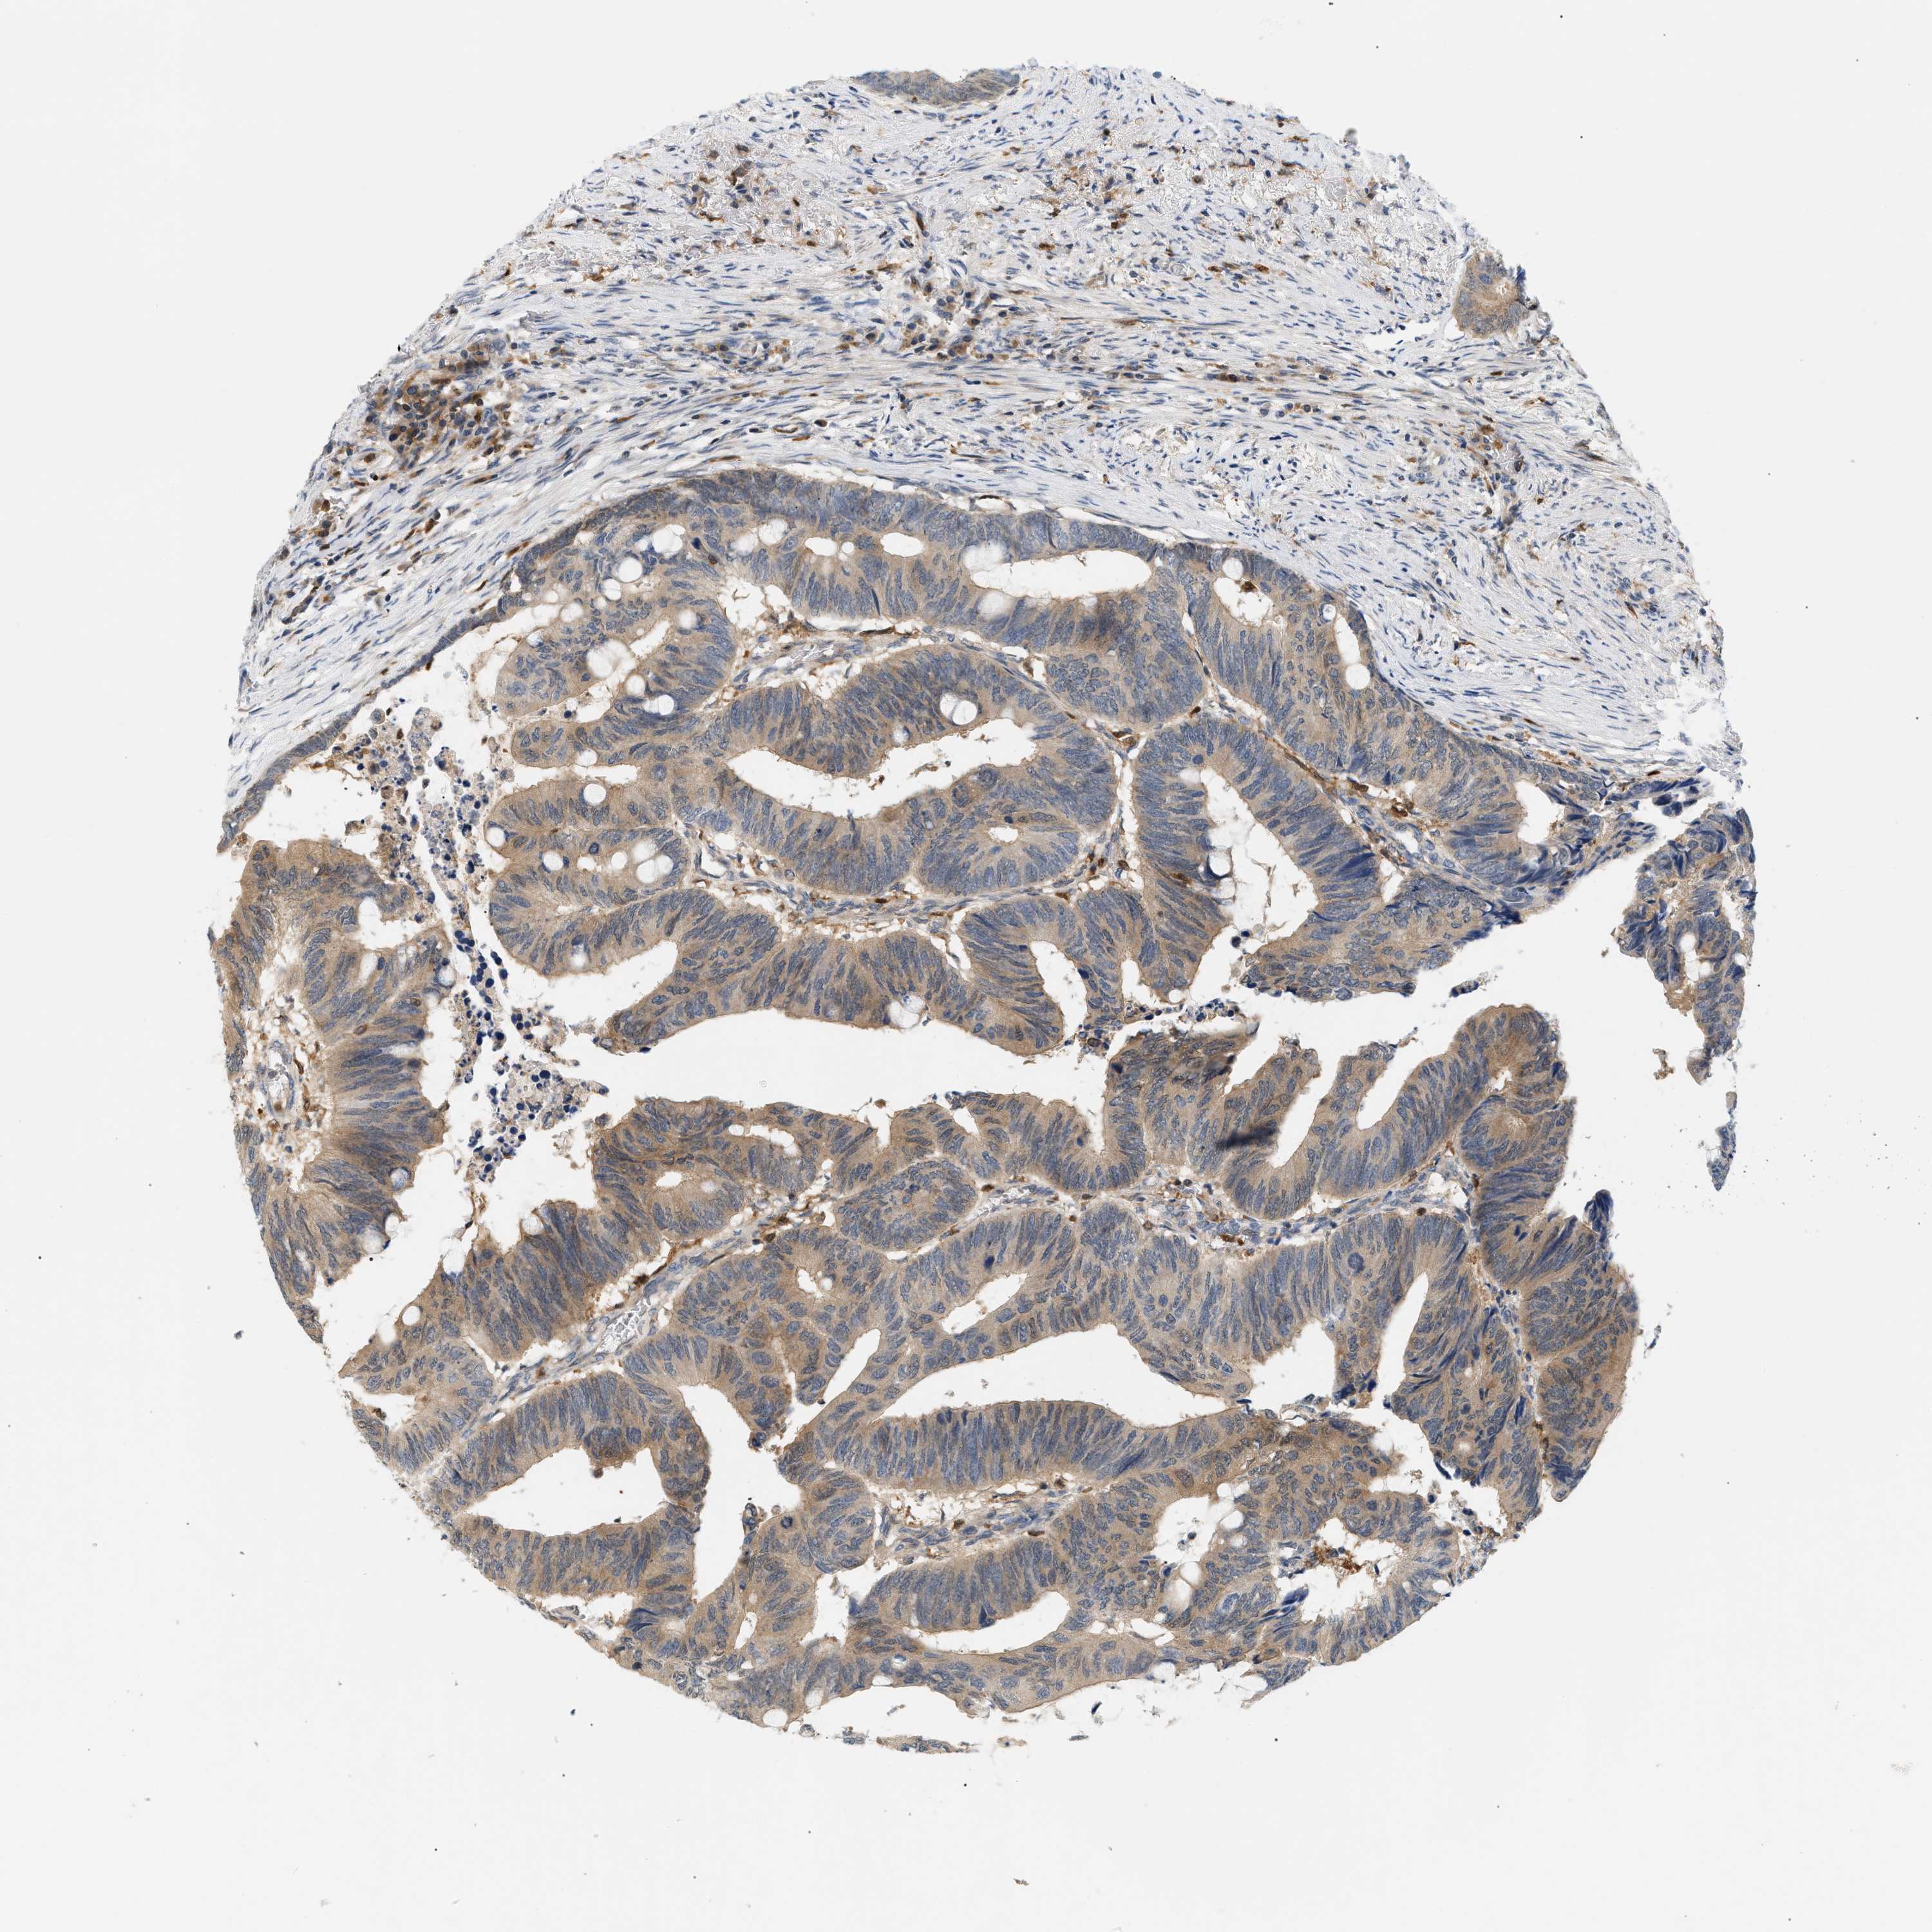

CANCER COLORECTAL CANCER Show tissue menu

Colorectal cancer

Human cancer